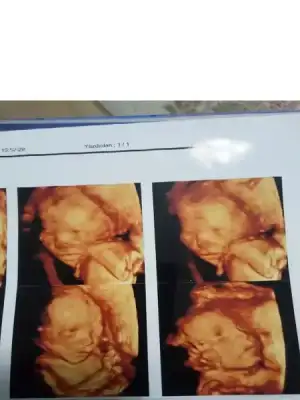

Kızlar dün detaylı ultrasonum vardı babası da bende kızımızı gördük. sağlık ile alakalı hiçbir sorunu yok herşey çok iyi dedi doktor

PELİN.webp